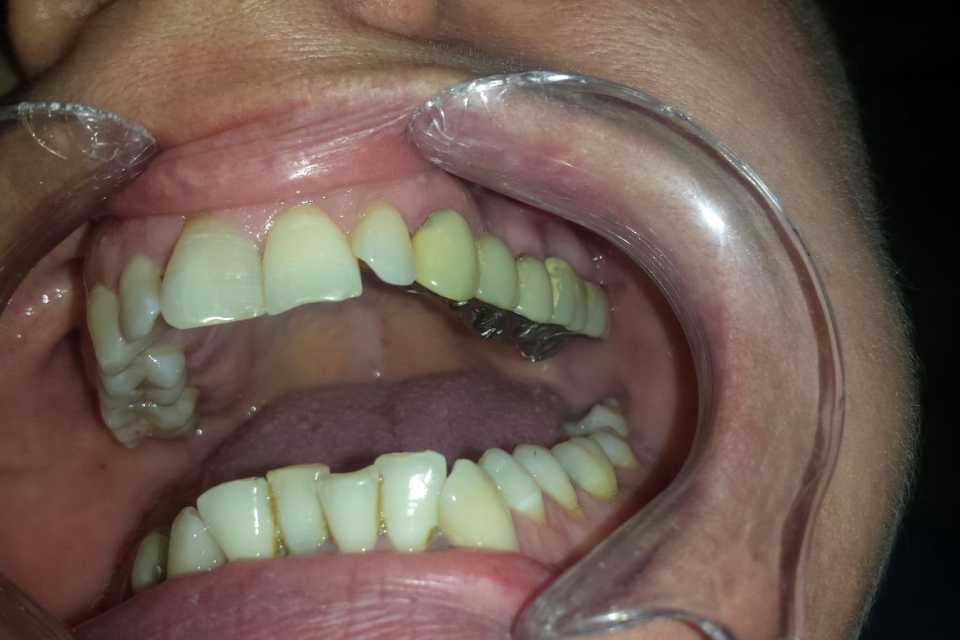

Pacienta s-a prezentat în cabinet din motive estetice și funcționale, acuzând sângerări gingivale și un miros neplacut. Am îndepărtat vechea lucrare, am refăcut tratamentele de canal, bonturile protetice și am slefuit bonturile cu prag.